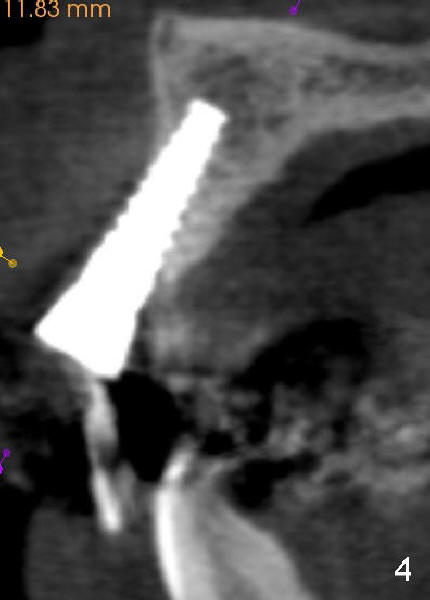

Segmental Osteotomy for Misplaced Implant

This corrective surgery was performed by Dr. Bernee Dunson.

Xin Wei, DDS, PhD, MS 1st edition 12/21/2011, last revision 12/23/2011